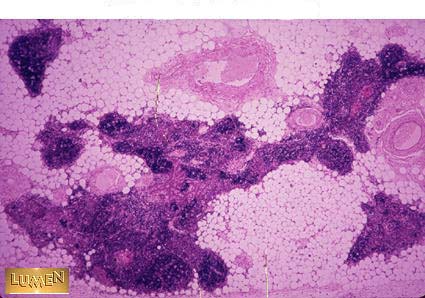

What organ is this? Be Specific!

Answer

Old Thymus